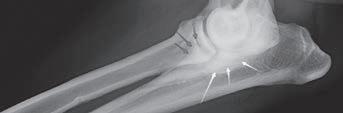

(A, C) Se observan múltiples nódulos (flechas) en serosas correspondientes a metástasis.

Figura 4. (A) Aspecto de la cavidad abdominal durante la necropsia una vez aspirado el líquido efusivo. Se observa una masa de grandes dimensiones (*). (B) Masa abdominal (*) relacionada con órganos abdominales. (C) Carcinomatosis (flechas) en mesenterio. (D) Carcinomatosis (flechas) en serosa de colon.